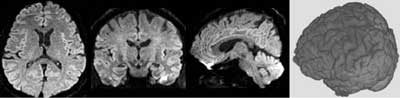

すでに開発ずみのアプリケーションとしては、脳の解剖構造を三次元表示した上に脳内の神経線維を重ね合わせて色分けしたカラーマップを、さまざまな断面から観察可能な"異方性カラーマップ(Tractography with Volume Color-coded map:TACVOC)法"があります。病変部と正常組織との境界部が把握しやすいので、脳腫瘍の術前の評価に有用だと思われますが、あくまでも研究用として開発したものですので、現在、臨床的有用性については検証中です。また、GE社とわれわれが共同開発したアプリケーションとして、"Volume Diffusion Imaging"があります。佐々木真理先生が2006年のRSNAで「Whole-Brain Volume Diffusion-weighted and Diffusion Tensor Imaging:Technique and Clinical Applications(全脳容積拡散強調・拡散テンソル画像:技術と臨床応用)」の演題で発表し、"Certificate of Merit"を受賞していますが、拡散強調画像で初めて全脳を高分解能で撮像できるようになりました。通常は3mmスライス厚程度で撮像しますが、"Volume Diffusion Imaging"では約1.6mm等方性ボクセルで撮像できます。頭蓋底部の画像の歪みや磁化率アーチファクトが大幅に軽減でき、冠状断面の画質が改善されます。

volume DWI